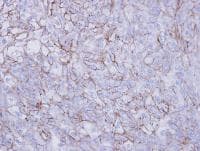

Rabbit Polyclonal Desmoglein 2/DSG2 antibody. Suitable for WB, IHC-P, ICC/IF and reacts with Human, Mouse samples. Immunogen corresponding to Recombinant Fragment Protein within Human DSG2 aa 1-200.

Applications ICC/IF, IHC-P, WB